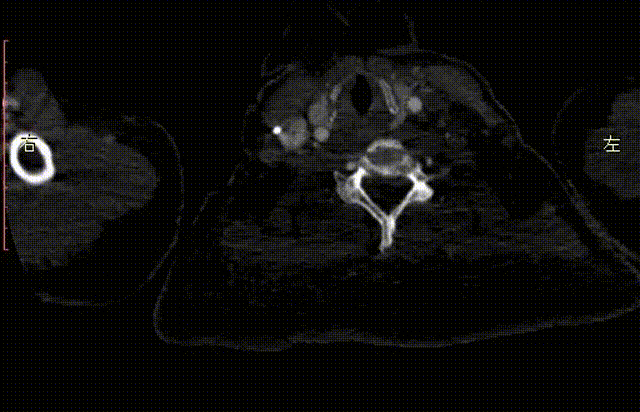

CTA检查

1、Ⅲ型弓,主动脉弓部远心端可见夹层动脉瘤,瘤体44mm*79mm,左锁骨下动脉发自瘤体下方降主段,且萎缩狭窄。

2、右椎动脉绝对优势,左椎动脉萎缩狭窄。